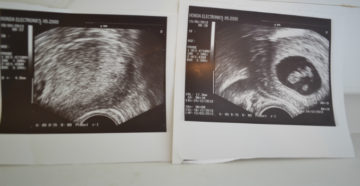

Основные задачи УЗИ на 8 неделе беременности Практически каждый определенный период во время беременности требует…

8 неделя беременности — В положении 1 8 неделя беременности: что происходит с малышом и…